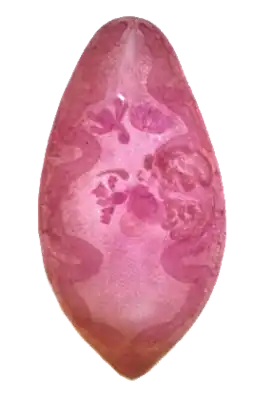

Paragonimus ist eine Gattung der Saugwürmer, die auch als „Lungenegel“ bezeichnet werden. Sie ist die einzige Gattung innerhalb der Familie Paragonimidae und enthält über 30 Arten. Zehn davon können auch den Menschen befallen, wobei der in Südostasien beheimatete Paragonimus westermani am häufigsten vorkommt.[1] Weitere humanpathogen bedeutsame Arten sind in Afrika Paragonimus africanus und Paragonimus utero-bilateralis und in Amerika Paragonimus kellicotti. Auch andere krebstierfressende Säugetiere werden befallen. Die Erkrankung wird als Paragonimiasis bezeichnet. Die Adulten treten in Zysten in der Lunge des Wirts auf. Infektionen können ohne Symptome verlaufen, aber auch tuberkuloseähnliche Krankheitsverläufe mit Bluthusten, Brustschmerz und Fieber sind möglich. Metazerkarien können auch in anderen Organen auftreten und dort Schäden verursachen.[2]

Die Vertreter der Familie sind bohnenförmige Plattwürmer mit einer Größe von 7–12 × 4–7 × 3–5 mm. Namensgebendes Merkmal ist die links der Mitte liegende Genitalöffnung (altgriechisch para ‚neben‘ und gonimus ‚erzeugend‘, vgl. Gonade).[2]

Die Außenhülle ist mit Stacheln besetzt, der Mundsaugnapf hat etwa die gleiche Größe wie der Bauchsaugnapf. Letzterer liegt vor dem Äquator. Der Ösophagus ist kurz, die Darmgabel liegt im Vorderkörper. Die beiden Bliddärme verlaufen wellenförmig und enden blind nahe dem Körperende. Die beiden großen Hoden sind gelappt und liegen etwa nebeneinander in der hinteren Körperhälfte. Cirrus und Cirrussack fehlen. Der Samenleiter erweitert sich zu einem geraden oder gebogenen Samenbläschen. Der Ductus ejaculatorius mündet auf der gemeinsamen Geschlechtsöffnung nahe des Hinterrands des Bauchsaugnapfs. Die Ovarien sind gegliedert und liegen beidseits nahe des Bauchsaugnapfs. Ein Laurer-Kanal ist vorhanden. Das Receptaculum seminis hat die Form einer sackartigen Bucht nahe der Basis des Laurer-Kanals. Der Uterus liegt im mittleren Körperdrittel seitlich der Ovarien und endet in einem kurzen Metraterm. Die Eier sind groß, die Dotterfollikel baumartig, umgeben die Blinddärme und erstrecken sich über nahezu den gesamten Körper fast bis zur Mittellinie. Das Ausscheidungsbläschen ist lang und röhrenförmig und erreicht fast die Darmgabel.[3]